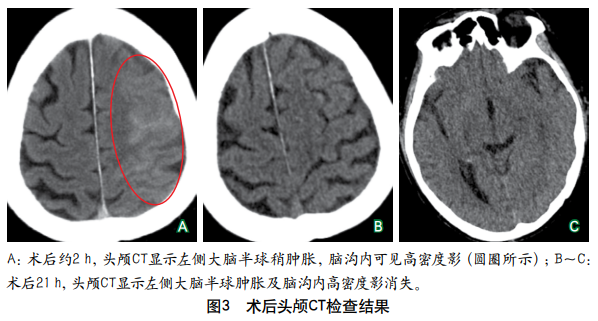

摘要:肥大性下橄榄核变性在临床上较为罕见,其典型临床表现包括腭肌阵挛、共济失调、声音嘶哑和眼部症状,而以四肢阵发性震颤为突出表现的患者则更为罕见,此类患者易被漏诊或误诊。本文报道1例继发于脑干(右侧脑桥和中脑)出血、以四肢阵发性震颤为突出表现的肥大性下橄榄核变性患者,介绍其诊断、治疗及随访情况,并结合相关文献探讨此类患者的临床特点,总结其解剖基础、影像学表现、诊断与治疗要点,以提高临床医师对该病的